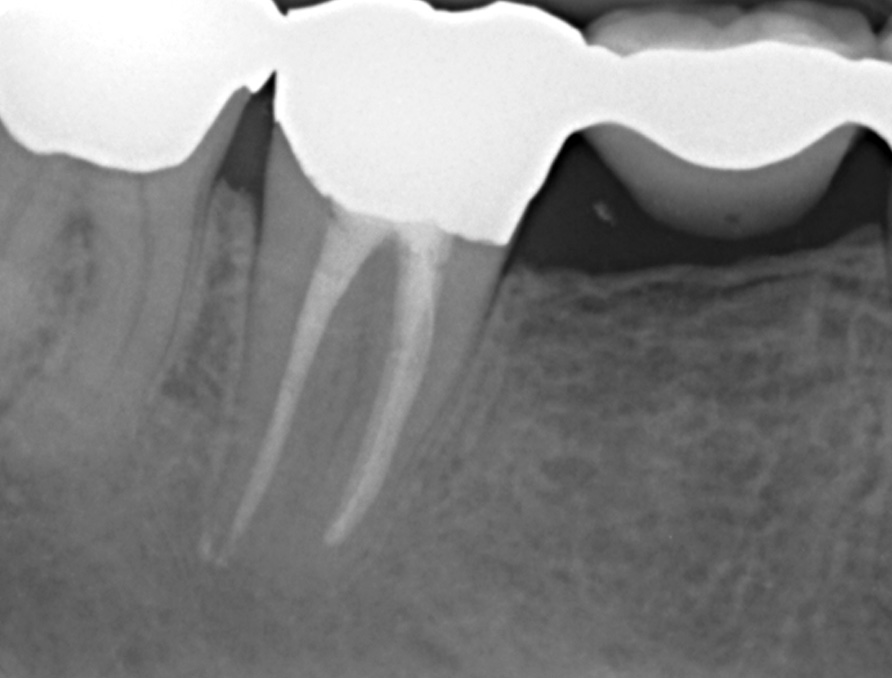

Langzeitkontrolle

Langzeitkontrolle nach 14 Monaten im Februar 2004. Röntgenologisch deutliche Heilungstendenz mit unauffälligem Parodontalspalt physiologischer Breite. Die Sealerüberpressungen ( Puff’s) werden resorbiert

Langzeitkontrolle nach über 11 Jahren im Juni 2013. Röntgenologische Ausheilung mit unauffälligem Parodontalspalt physiologischer Breite.